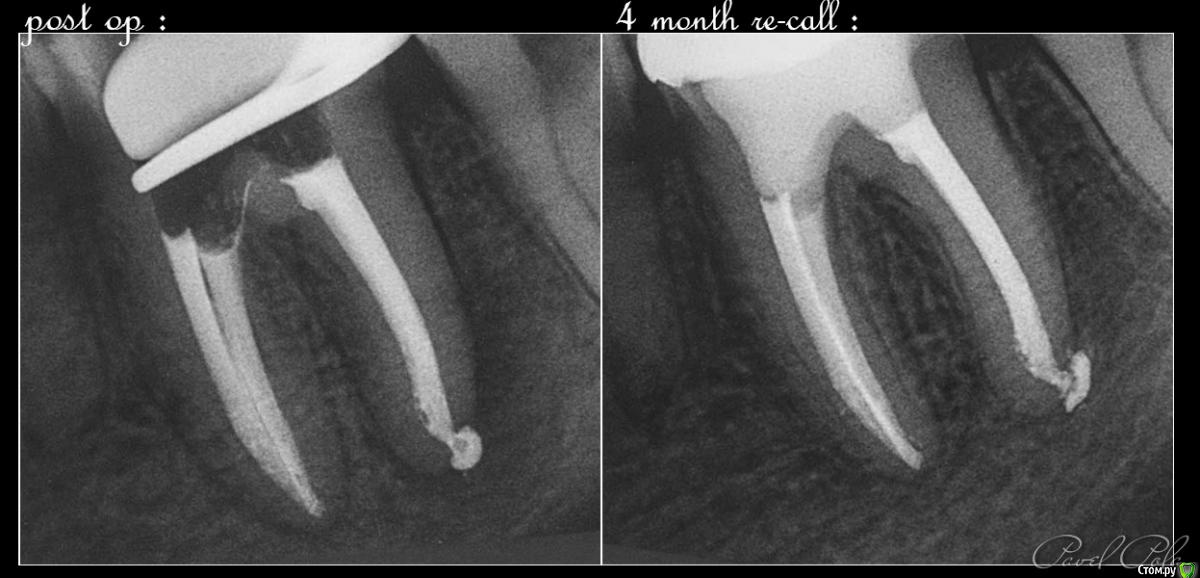

M@estro Опубликовано 23 июля, 2015 Автор Поделиться Опубликовано 23 июля, 2015 И сюда закину Жалобы на боли, КЕСТУ и желание " удалить " . Зуб 3.6 . Пациент - парнишка 16 лет. Зуб ранее пытались лечить,парень признался, что было больно, и больше он туда не вернулся, а в другой клинике предложили удалить зуб , ибо "кЕста". Перкуссия - резко-болезненна , в полости зуба - остатки ватки. В первое посещение - билд, обработка каналов ( дистальный 70/02 , медиальные 50 / 02) , антисептика, кальций на 2 недели . Второе посещение - обтурация , в дистальном -" неаккуратненько", плюнул силер. Следом бюджетная мк коронка. Контрольный через 4 месяца. 9 Ссылка на комментарий